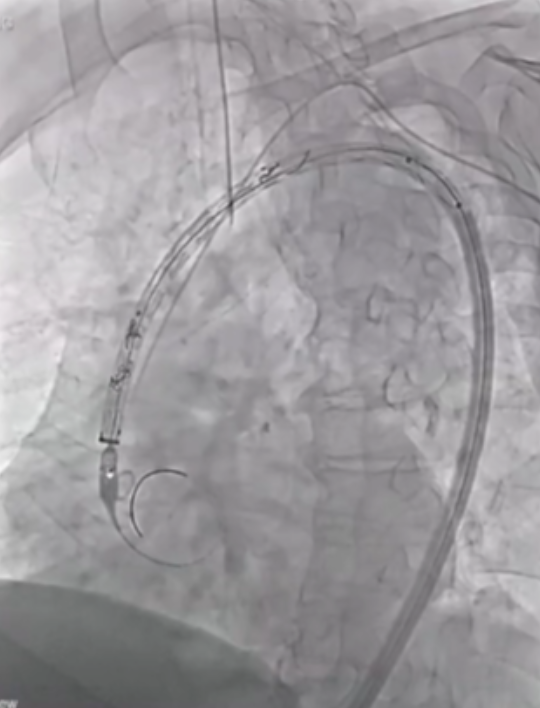

在近端密封区选择上,通常需向近端延伸25-30mm以实现更优密封效果,而定制器械凭借开窗设计,能有效增加密封长度。定制化支架技术也至关重要,支架必须精准定位,标记移动易引发开窗错位;同时要做好旋转控制,否则支架旋转不良会提升逆行夹层风险。一旦出现开窗对齐问题,可能导致I型内漏,且长期处理难度大,需借助更复杂的穿通技术纠正分支位置。

第二代分支支架在设计上进一步优化,Cook LSA分支支架(Gen2)采用三角形凹槽设计,要求左颈总动脉与左锁骨下动脉间距25mm,分支开口与织物端距离60mm,其预装导管系统使分支接入更简便,为临床操作提供了便利。

在主动脉介入治疗领域,支架设计持续创新。Terumo双分支支架采用大型矩形凹槽设计,即便旋转90度,仍能顺利接入分支,对于弓部曲线较为紧张的情况适配性更强。不过,该支架也面临技术挑战,手术中需要精准控制支架的旋转与对齐,以确保治疗效果。